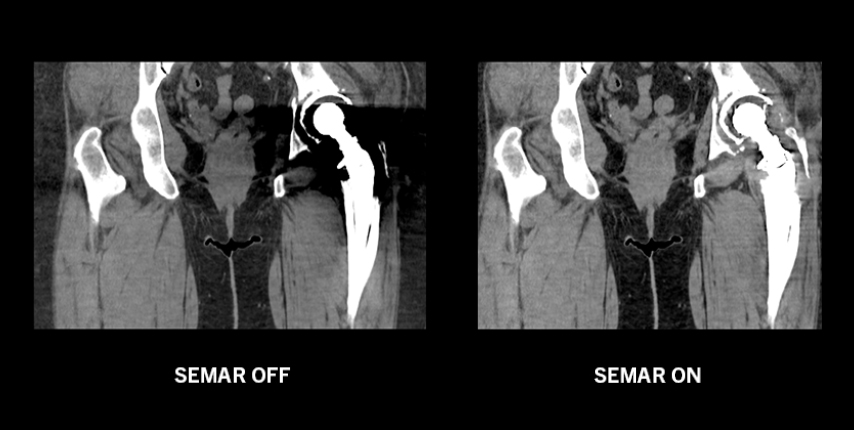

Single Energy Metal Artifact Reduction

SEMAR

Canon Medical Systems' SEMAR (Single Energy Metal Artifact Reduction) utilizes a sophisticated iterative reconstruction technique to reduce metallic artifact, improving visualization of implants, supporting bone and the adjacent soft tissues for a clearer and more confident diagnosis. SEMAR can be set in the scan protocol so the reconstructions are fully automatic requiring no additional operator input.